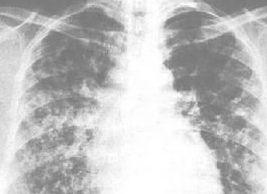

本病主要病原體為肺炎支原體,通過飛沫傳播,偉染源為患者及恢復期帶菌者。全年皆有發病,寒冷季節較多。發病年齡多在5-9歲,其次為10-14歲。臨床表現潛伏期2-3周,臨床表現多種多樣,一般起病不甚急,體溫在37.5-41℃可為持續熱或弛張熱,或僅有低熱、甚至不熱,持久的陣發性劇烈咳嗽為突出表現。吐粘液性痰,少數病人痰中帶少量血絲,部份病兒伴廣泛性胸痛。常有畏寒、頭痛、厭食等。一般不伴呼吸困難,但嬰幼兒可表現為毛細支氣管炎徵象。胸部體徵不明顯,X線表現與體徵不相稱。肺部陰影可呈片狀、雲霧狀、網狀,粟粒狀或間質性浸潤。20%患兒有少量的胸腔積液,短暫的肺不張、肺氣腫。病程3-4周,吸收緩慢,有長達數月至一年者,甚至留下肺功能減退,常有復發,血冷凝集試驗等有助病原診斷。紅黴素,四環素治療有效。